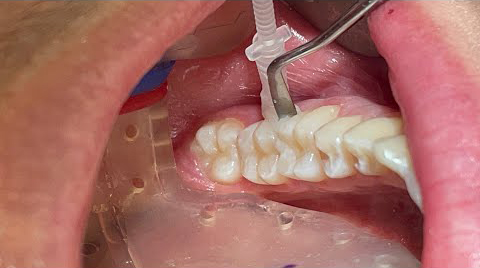

Curodont-Repair-Fluoride-Plus-Our-experience-has-been-extremely-positive_1

Dr. Parsons applying Curodont

Curodont application